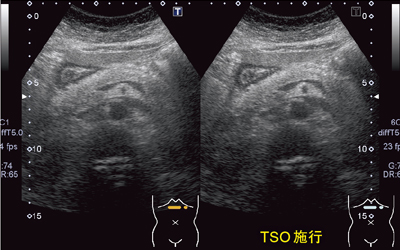

また,腹部への適応を見るため,軽度の肥満,脂肪肝のある被検者に,TSOのマイナス補正を施行した(図7)。マイナス補正とは音速の遅い組織に合わせた補正であるが,画像がシャープになり,特にSMA(superior mesenteric artery)の血管腔などはきれいに抜けるように描出され,腹部領域にも有用であると考えられる。図8は,C型慢性肝炎により肝臓が硬くなっている症例である。この場合は,音速が速い組織に対応するためにTSOをプラス補正することで,肝内の石灰化や腎被膜の構造などが明瞭に描出される。

図7 60歳代,女性,軽度肥満,脂肪肝の症例 TSOをマニュアル調整でマイナス補正することで画像が シャープになった。

図7 60歳代,女性,軽度肥満,脂肪肝の症例

TSOをマニュアル調整でマイナス補正することで画像が

シャープになった。

図8 70歳代,男性,C型慢性肝炎の症例 音速が速い組織に合わせてTSOをプラス補正することで シャープに描出された。

図8 70歳代,男性,C型慢性肝炎の症例

音速が速い組織に合わせてTSOをプラス補正することで

シャープに描出された。